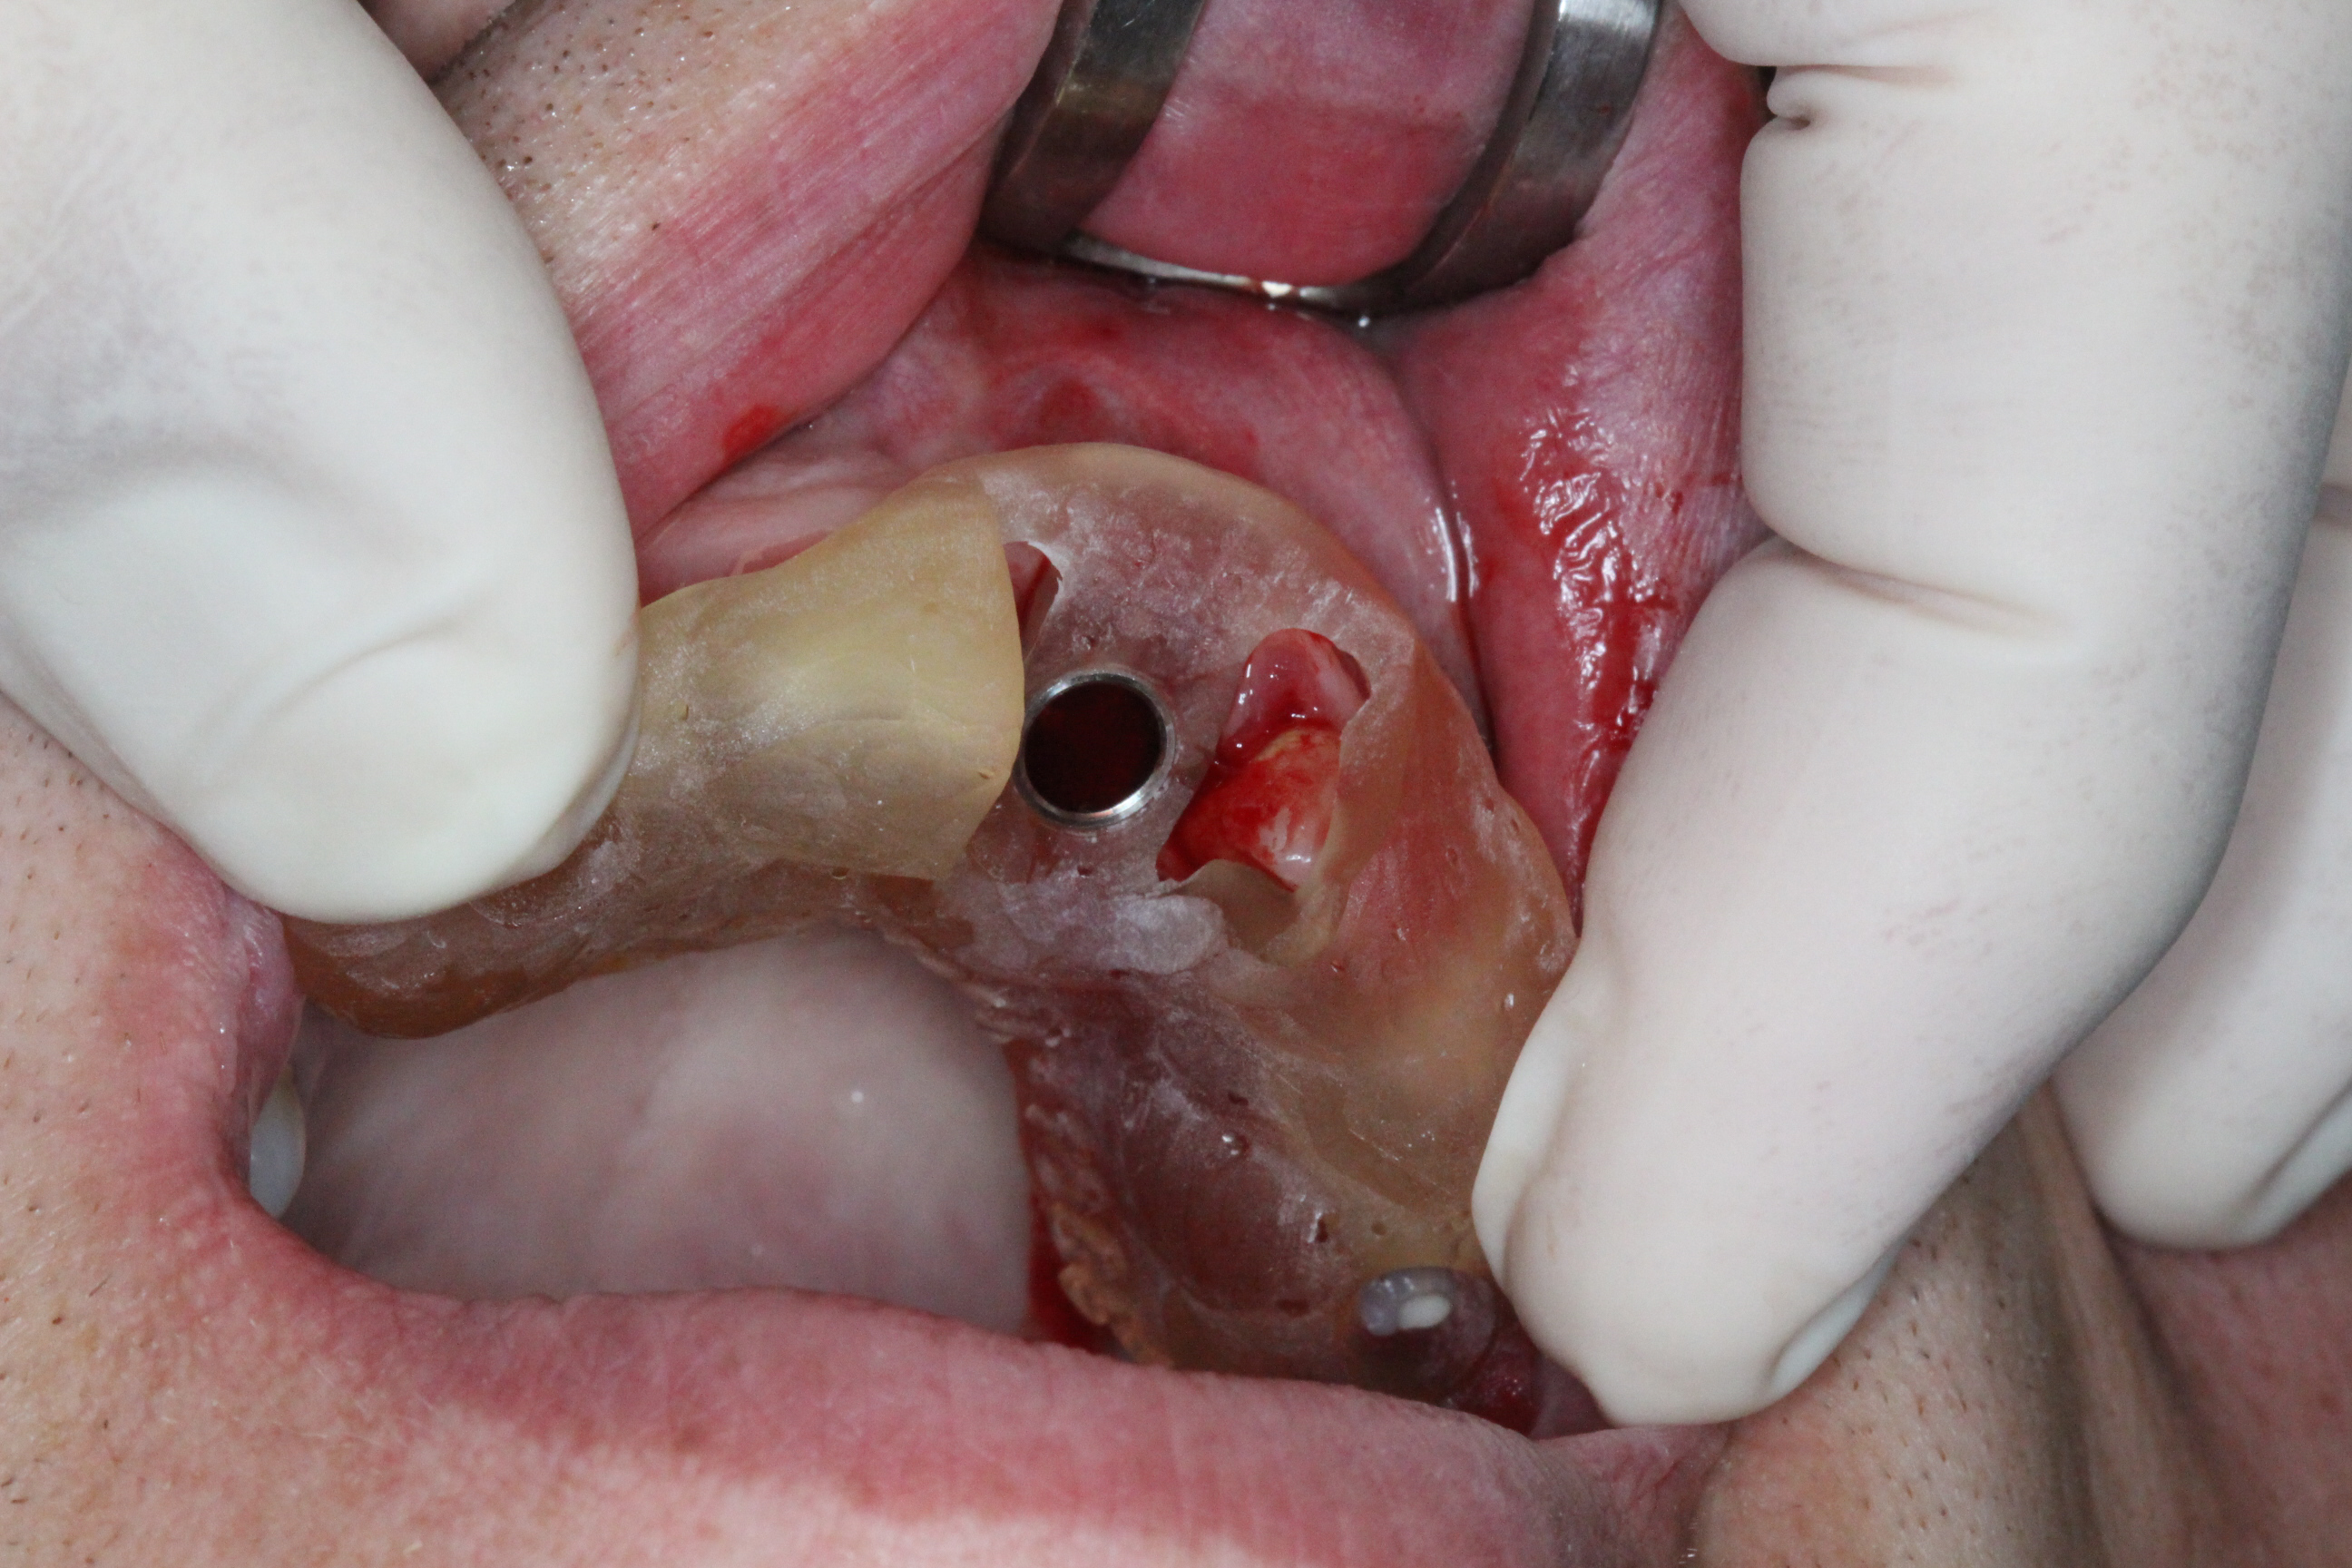

An atraumatic extraction of tooth 21 was performed without flap elevation in order topreserve the soft tissue architecture.

The DICOMLAB surgical guide was positioned, and the implant was placed according to the digital plan.

Implant placed: DSI Conical Implant – 4.3 × 13 mm.

Primary stability achieved: 45 Ncm insertion torque.

Achieving this level of stability and ideal prosthetic positioning would have been extremely difficult without guided surgery due to the severe buccal bone deficiency.

The prosthetic phase was performed by Dr. Simon Budak.

A Multi-Unit Abutment (MUA 1.6) was connected to the implant. Using a titanium sleeve, a temporary crown was fabricated chairside, and the implant was immediately loaded. Benefits of this approach included preservation of the extraction socket, maintenance of the interdental papilla, immediate restoration of aesthetics, and high patient satisfaction.